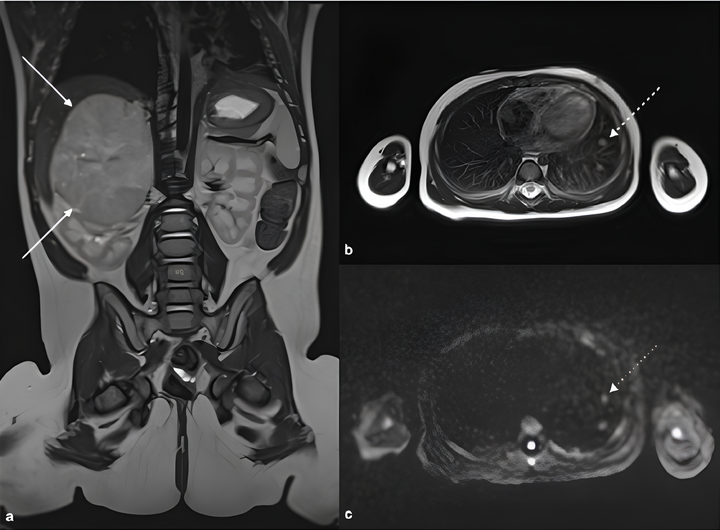

Пациент с синдромом Ли-Фраумени, у которого одновременно выявлены адренокортикальная карцинома и глиобластома (стрелки) (A).

Изображение всего тела, демонстрирующие опухоли (стрелки) в головном мозге и коре надпочечников (B).

Специализированная магнитно-резонансная томография головного мозга, показывающая глиобластому (стрелка) С